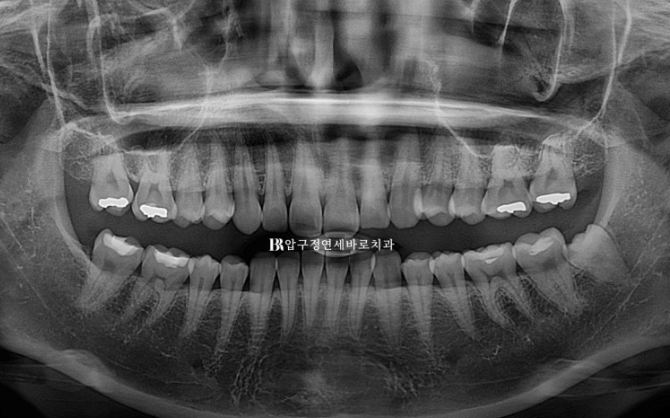

23.08

24.12

발치 공간으로 어금니 쓰러짐 없이 뿌리까지 평행하게 이동 된 것이 확인됩니다.

인비절라인으로 뿌리이동 안되나요?

아니요 잘 됩니다